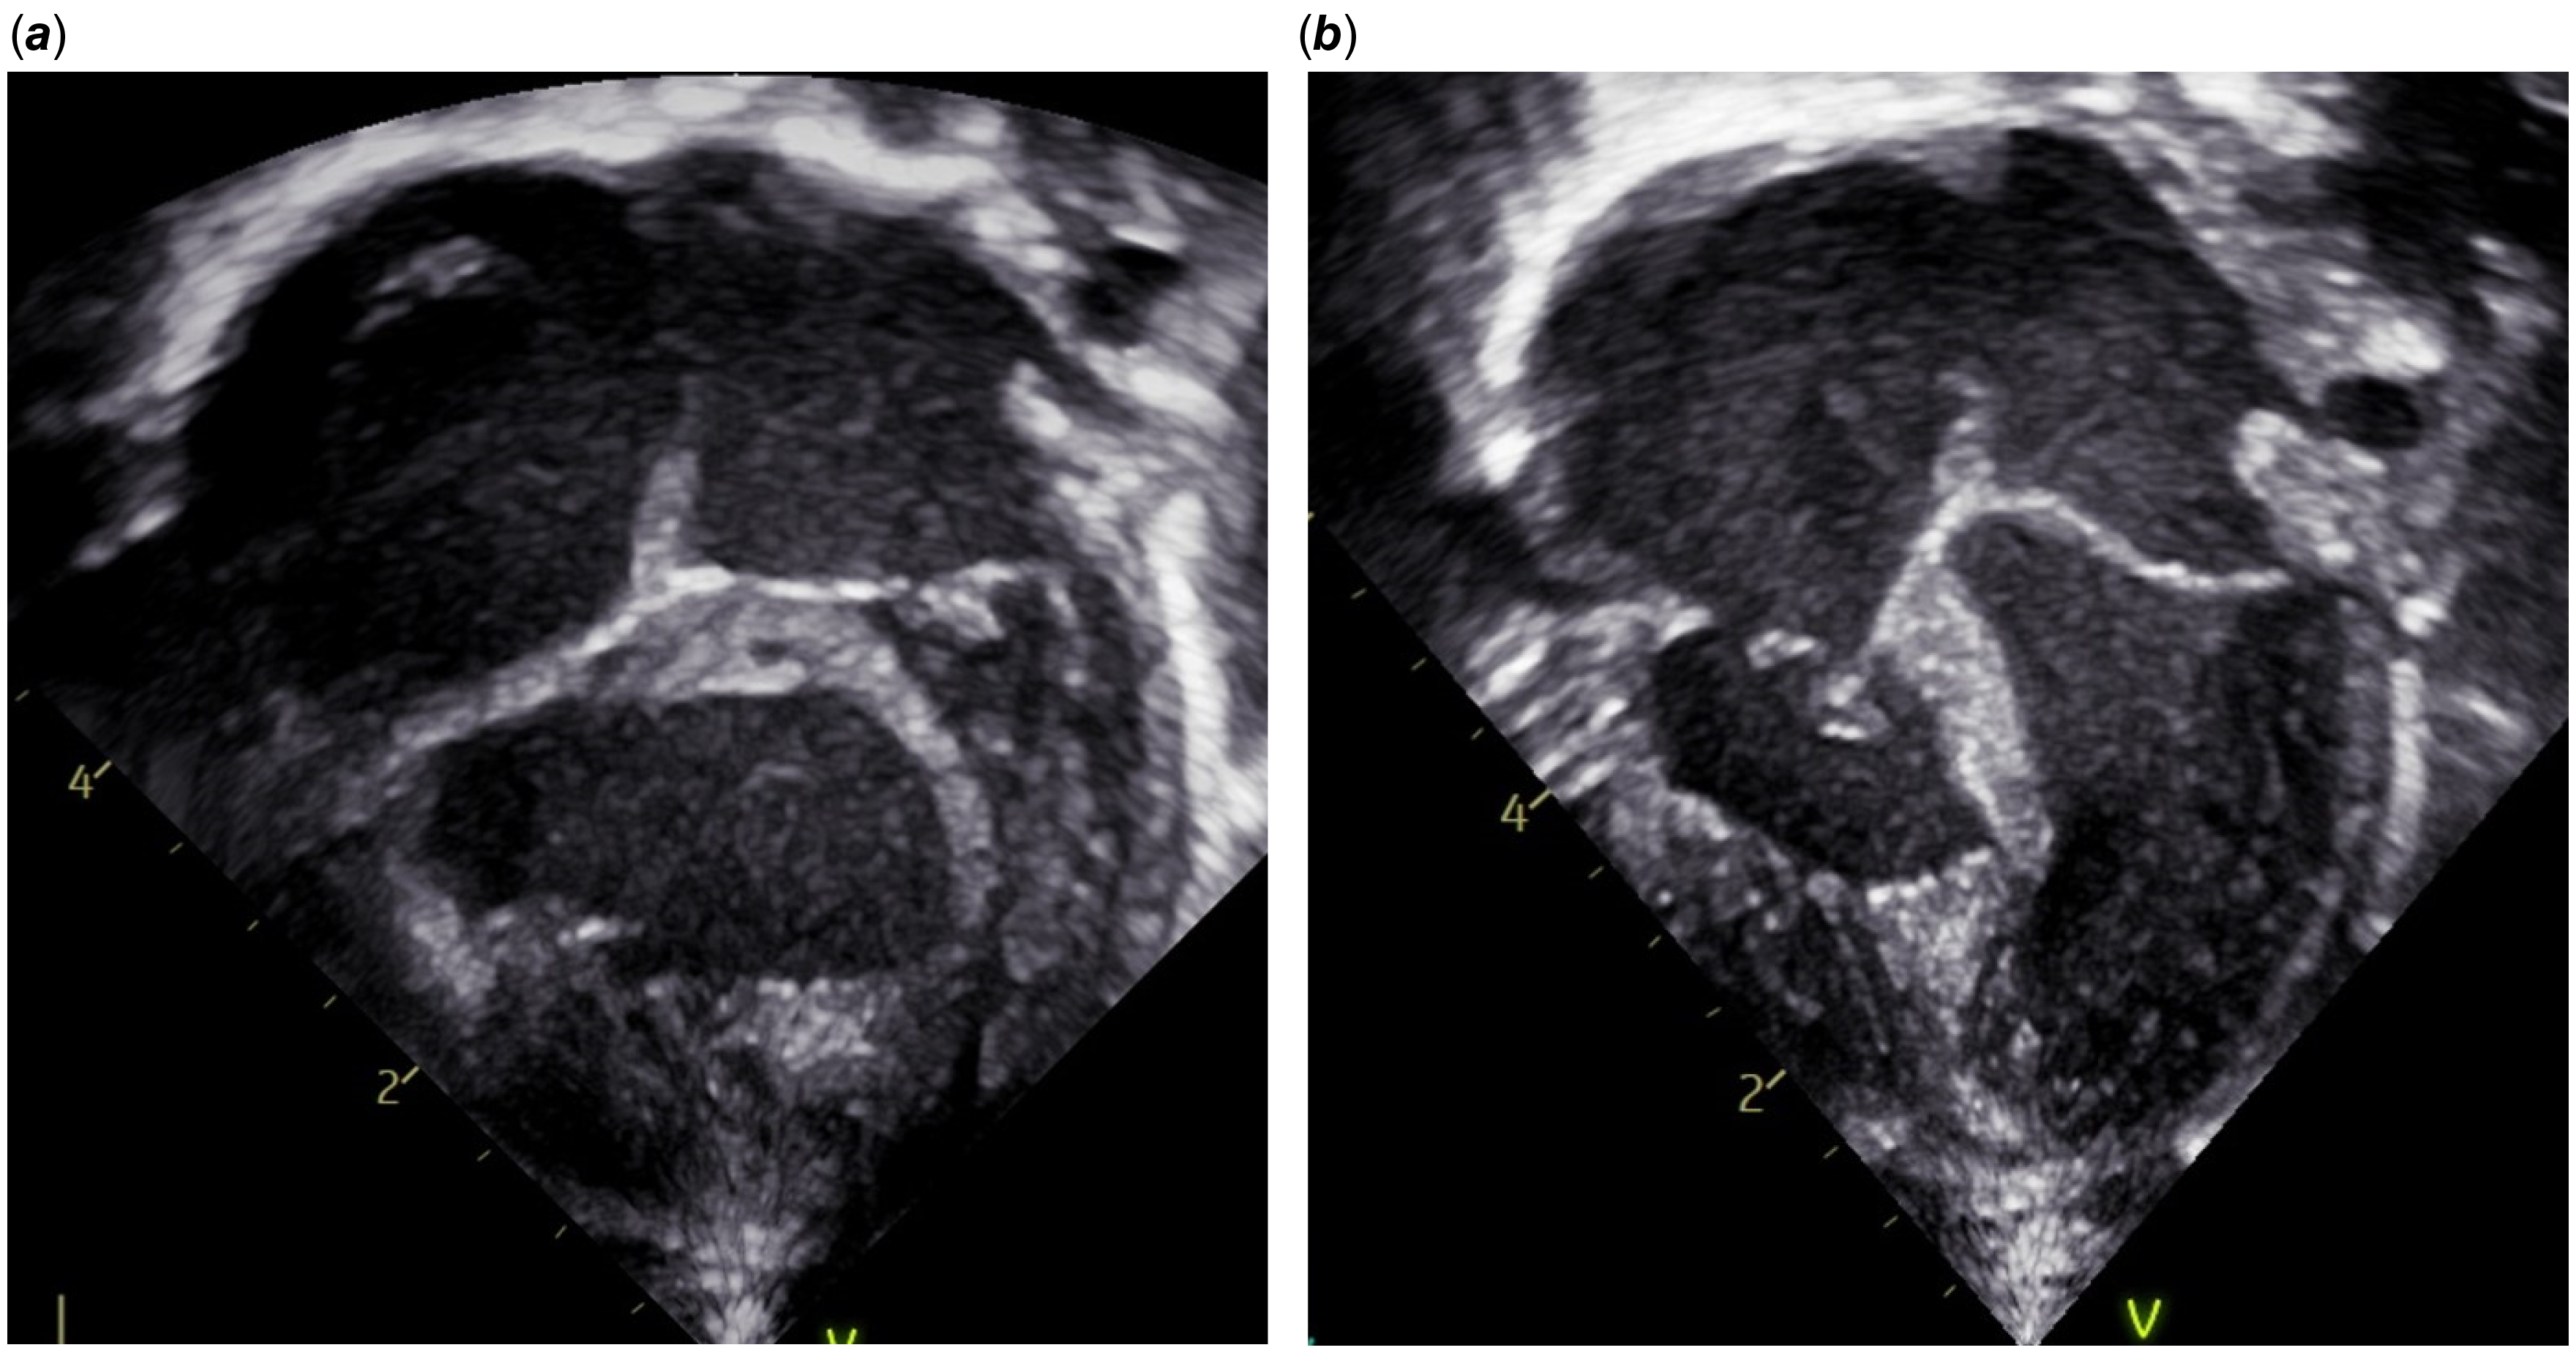

A chest X-ray showed oligaemic lung fields when compared to the film immediately following stent insertion (Fig. 1). Echocardiography showed the ductal stent was patent with laminar flow. To increase arterial saturation and promote pulmonary blood flow, the intensive care team administered a red blood cell transfusion, inhaled nitric oxide, and norepinephrine and epinephrine to raise blood pressure and increase left-to-right ductal flow. These interventions were unsuccessful in resolving the episodic desaturation. A pattern emerged during this resuscitation whereby intravenous fluid boluses consistently had the transient effect of increasing the oxygen saturation and blood pressure for 15–30 minutes at a time. An echocardiogram obtained during resuscitation showed that the hypertensive right ventricle was compressing the left ventricle (Fig. 2). The team concluded that right ventricular decompression would be advantageous in promoting both cardiac output and pulmonary blood flow.

Figure 2. (a) Apical four chamber view showing compression of the left ventricle by the hypertensive right ventricle . (b) Apical four chamber view after right ventricle decompression.

Review of the post-surgical echocardiogram showed improvement in right ventricular hypertension and septal bowing (Fig. 2), and an unobstructed right ventricular outflow tract. There was only mild tricuspid regurgitation with an estimated right ventricular pressure of 48 mmHg, which was 62 per cent of the systemic pressure. Oxygen saturations at the end of the case were 88–92%.